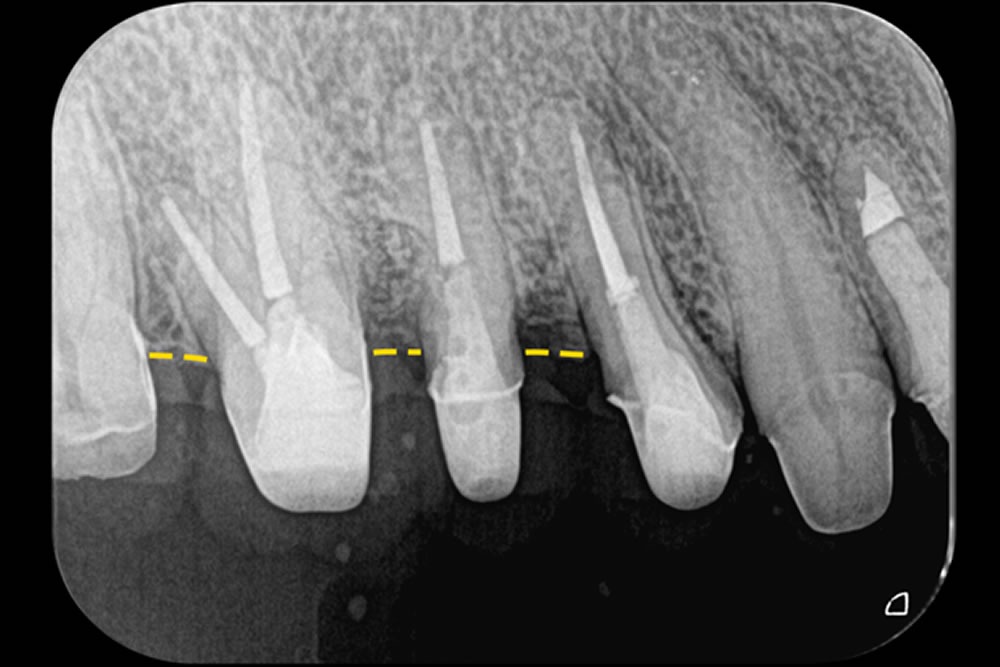

こちらの患者さまは、右上の奥歯(第一大臼歯)に歯周病による垂直的な骨の欠損と、歯の根元が分かれている「分岐部」にまで炎症が進行していました。このような状態では、通常のクリーニングや手術では改善が難しいケースです。

そこで当院では、できるだけ傷を小さくして体への負担を減らすMINST(最小侵襲手術)を採用しました。マイクロスコープ(顕微鏡)を使用し、分岐部をしっかり確認しながら、見えにくい部分に丁寧な切開を行い、視野を確保しました。

治療では、Er:YAGレーザー(エルビウムヤグレーザー)を用いて感染した組織を除去(デブライドメント)し、骨の再生を促す前処理(デコルチケーション)も同機器で行いました。治療から2年半が経過した現在も、歯と歯ぐきの状態は非常に安定しており、良好な経過をたどっています。